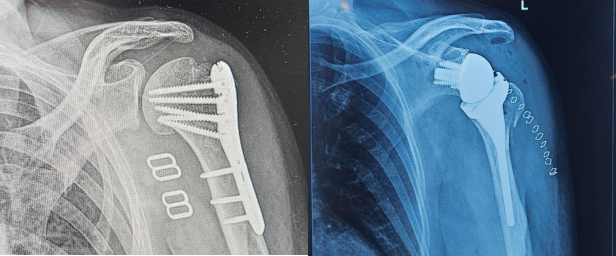

Discover pain-free living at our trusted Orthopedic and Shoulder Speciality Clinic, we provide advanced care for your bones, joints and muscles. Whether you are recovering from an...